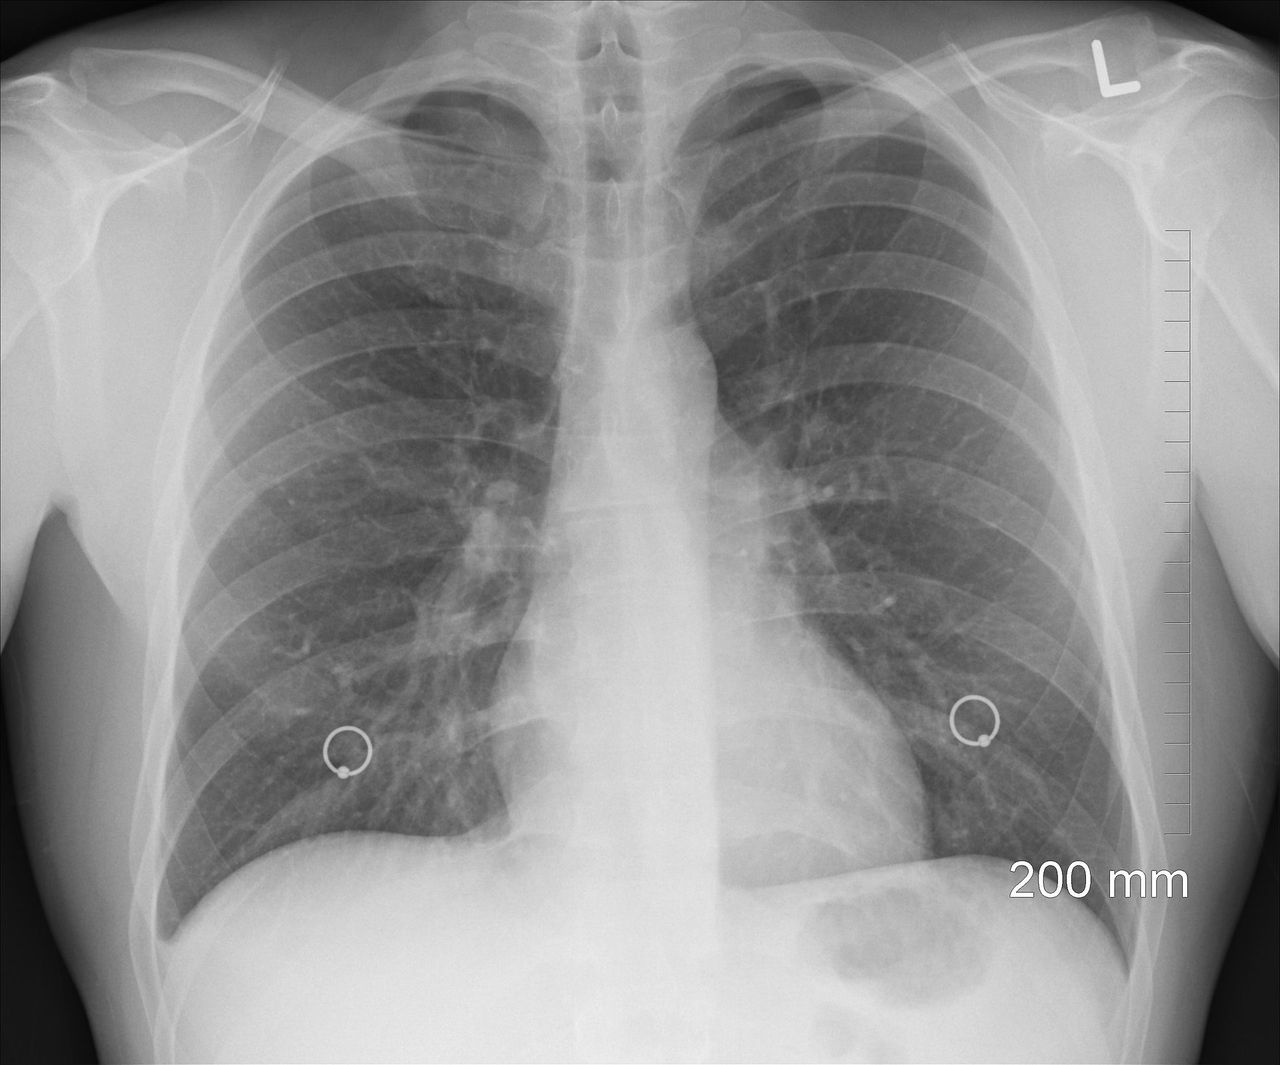

Zdjęcie rentgenowskie pozwala przewidzieć zgon

19 października 2018

Redakcja iPolska24